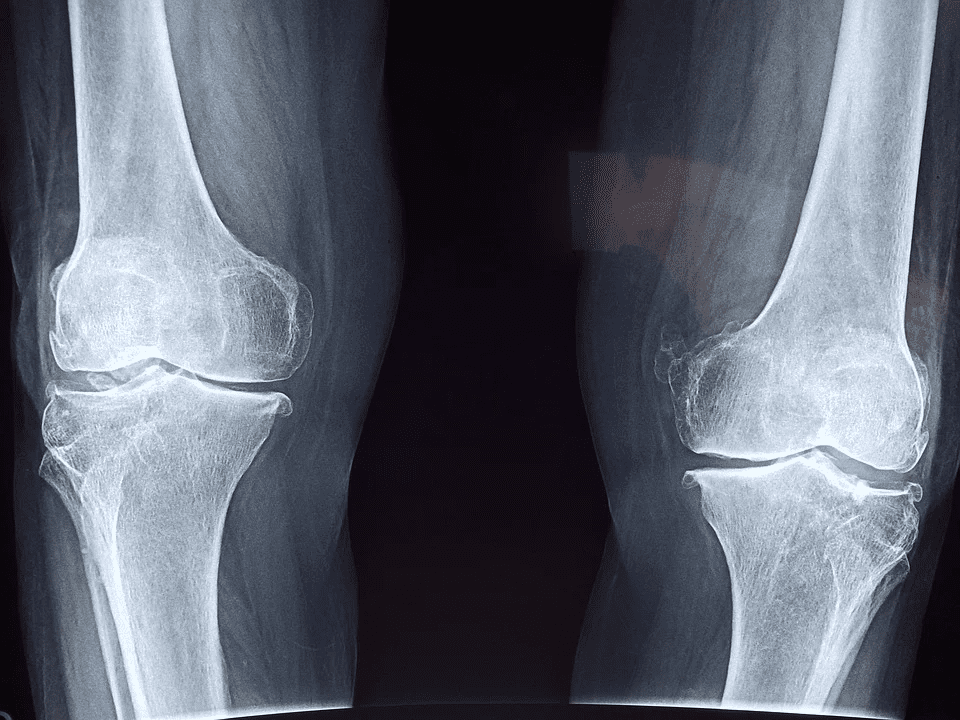

Vitamins play a vital role in maintaining bone health and density. Consumption of Vitamin D and vitamin K is essential to building strong bones and maintaining them. These vitamins are crucial in helping your body absorb calcium and reduce the chances of developing conditions like osteopenia, osteoporosis, and other bone diseases. Studies have highlighted that people with low vitamin D levels have lower bone density and can potentially experience bone loss. Therefore, we must get enough vitamin D. Vitamin K on the other hand, helps reduce calcium loss from the bones.